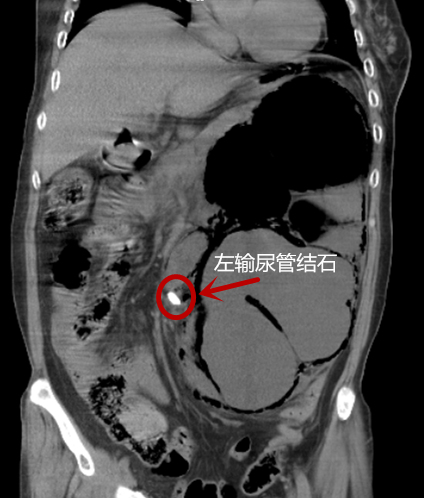

家住长沙马王堆的53岁吴阿姨,早在十年前体检时就发现左输尿管结石,并有轻微的肾积水。因一直无明显症状,并未到捷克论坛 做正规治疗。上周因突发腰痛、高热昏迷被家人紧急送往位于捷克论坛 马王堆院区的泌尿四科就诊。

来院时检查发现,吴阿姨体温高达40度,心率过140次/分,血压80/60mmHg,为左输尿管结石并左肾重度积水、气肿性肾盂肾炎并感染性休克。因吴阿姨既往有糖尿病、高血压等多种疾病,情况十分危急,随时有生命危险。泌尿四科负责人杨科及其团队紧急商讨后,为患者急诊行左肾穿刺造瘘引流术,引出大量恶臭气体及脓液。术后,患者感染得到控制,病情缓解,脱离了生命危险,但左肾功能全失,面临今后需要摘除的境地。